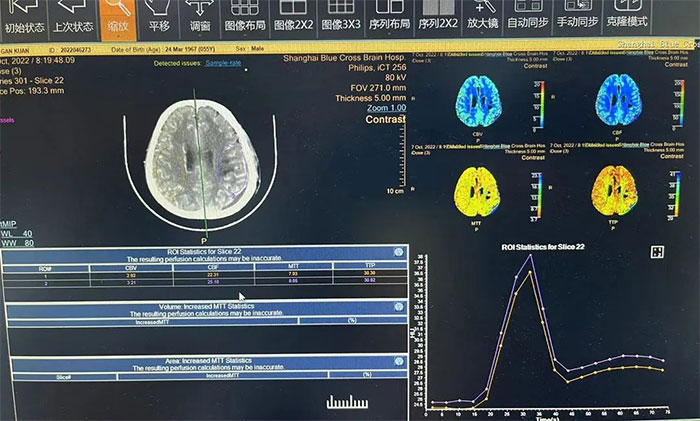

▲ 術(shù)后查CTP,左側(cè)大腦灌注明顯改善

術(shù)后,在6A病區(qū)醫(yī)護(hù)團(tuán)隊(duì)的精心治療和護(hù)理下,蘇先生恢復(fù)情況良好。再經(jīng)系統(tǒng)的肢體康復(fù)訓(xùn)練,不到半個(gè)月,右側(cè)肢體的運(yùn)動(dòng)功能也基本恢復(fù)了正常。